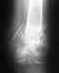

Приложил холод и поехал в районный травмпункт. Сделал рентген.

Врач поставил диагноз: "З/перелом 5 плюсневой кости б/с". Снимок мне, увы, не показал. Наложил лангету.Лечение - иммобилизация, без нагрузки, кальций+д3.

Сегодня 40 день (почти 6 недель) с момента перелома, сделали повторный снимок. И неожиданно врач говорит что "смещение стало меньше" и "сращение недостаточно". И прописал еще две недели в лангете. Однако при этом советует отказаться от костылей и ходить опираясь ПОЛНЫМ весом на всю ступню (а не только пятку, например). При этом у меня до сих пор сильные боли в районе мизинца (сбоку и снизу стопы) и гематома в половину ступни в районе трех центральных пальцев.

Прикладываю снимки рентгена на 40 день перелома.

Перелом срастается в приемлемом положении.

Можно увеличивать нагрузку на ногу в пределах переносимого. Смысла в гипсовой шине при полной нагрузке не видно - гипс немедленно сломается.